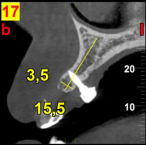

In our sample some mini-implants were inserted bicortically. In CBCT images at 5 year follow-up control it was noticed that the buccolingual width of the alveolar process had been totally preserved during growth (Figure 2). In addition,the described technique to replace the missing teeth also facilitates the later insertion of a dental implant as it maintains both morphology and density of the alveolar bone in that region .

Figure 2A. Initial sagittal cone-beam section of the alveolar process.

Figure 2B. Sagittal cone-beam section at 5 year follow-up.